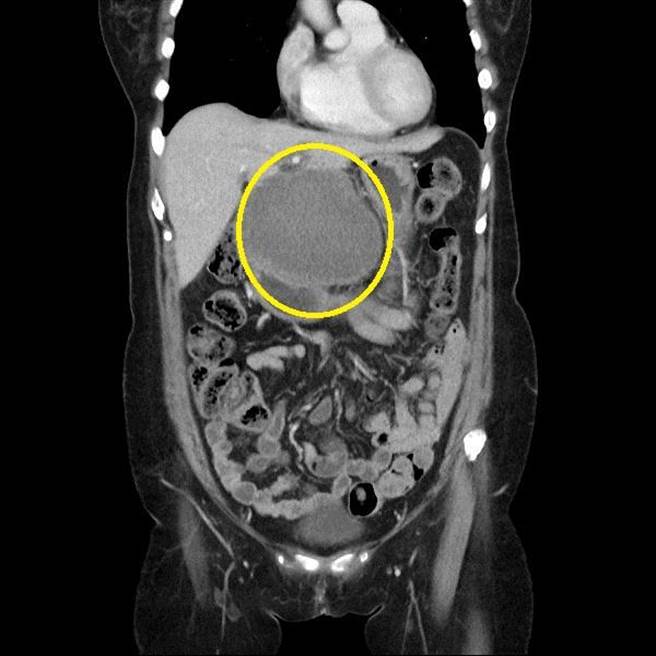

肝癌病患蔡婦術後電腦斷層,原本肝臟腫瘤已消散。(台中慈濟醫院提供/王文吉台中傳真)

「要解決這種痛苦,還是得用手術方式解決。」余政展決定切除病人左肝剩餘腫瘤,術後病理報告出來,切下的肝臟及腫瘤幾乎找不到癌細胞。

余政展表示,癌症病人一般透過影像學查測量腫瘤大小變化來評估治療效果,這位病人則是少見的在治療後有機會切除病灶,病理報告確認沒有活的癌細胞,代表免疫療法加標靶治療對蔡女士控制效果非常好,腫瘤完全消失。